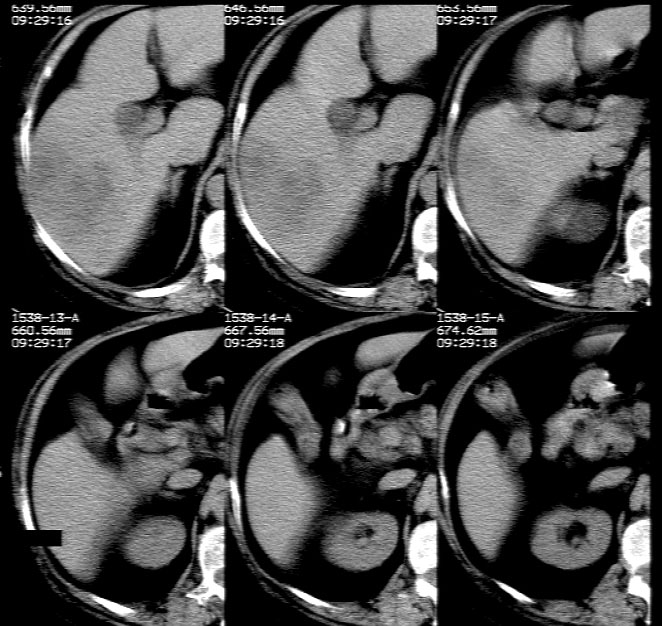

患者 女 80岁 二型糖尿病 低热/腰酸4天入院。b超:肝硬化/胆脾胰正常。白细胞12.87 中性74.6 淋巴20.6  单核3.6 。  ct特征较少,怎样理解此影像,请同仁讨论。下附ct报告。

平扫示: 肝右后叶见团状低密度灶,边界欠清,密度略不均匀,ct值28-32hu,肝内胆管无扩张。

ct增强扫描示: 动脉期肝右后叶团状低密度边缘明显不均性强化,内呈不规则峰窝状低密度(无强化区),不规则分隔亦见明显强化;三期扫描像均见,病灶有明显占位征,周围血管、胆管推挤外移,病灶与正常肝组织分界不清,延迟期病灶周围见雾状略低密度(较肝左叶)。

肝右后叶团状低密度占位性病变,结合临床提示: 1、肝脓肿? 2、不排除肝ca可能。建议afp检查。